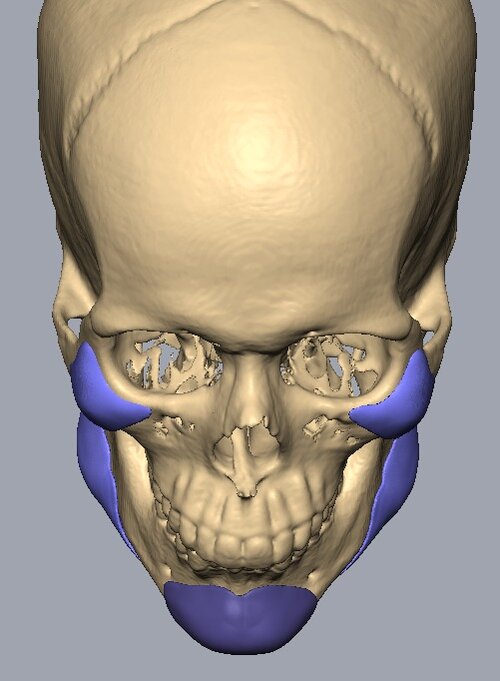

Recieved the draft 1 of the design, what changes should i ask for?? a couple of things i can think of are malar implants not giving enough lateral protrusion, gonion flaring.

I also am planning to include infra implants as well.